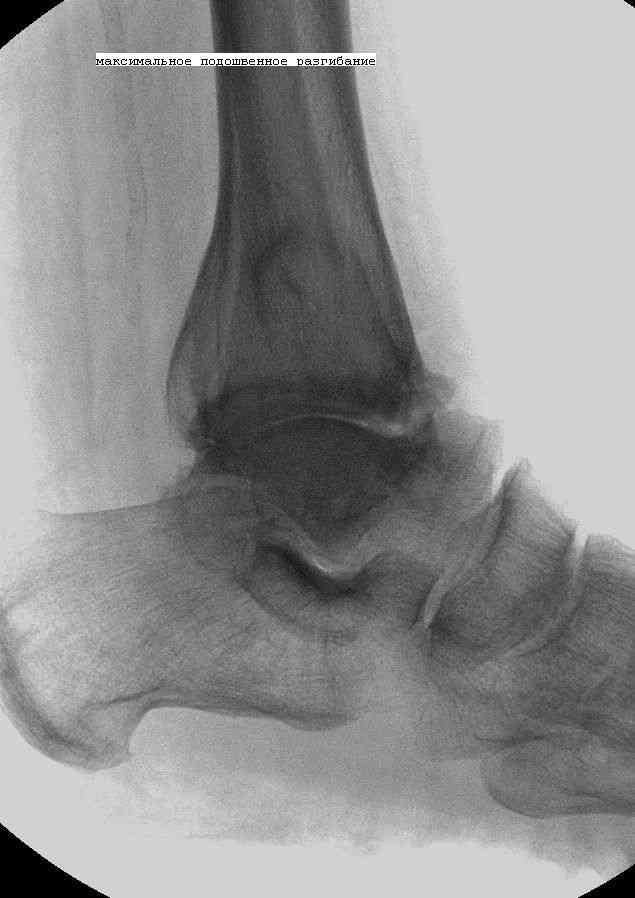

Эндопротезирование или артродезирование ?К нам обратился пациент 73 лет с жалобами на боли и деформацию в области левого голеностопного сустава. В анамнезе: в 1980 году перелом обеих лодыжек с вывихом стопы кнаружи. Лечился консервативно: одномоментная репозиция переломовывиха в левом голеностопном суставе с трансартикулярной фиксацией голеностопного сустава спицами Киршнера через пяточную, таранную, большеберцовую кости. Накладывалась гипсовая иммобилизация. Даная манипуляция осложнилась нагноением с развитием гнойного артрита. Были удалены спицы, сустав со слов больного, промывался растворами, но не вскрывался, получал антибиотики. Гнойный процесс был купирован, и рецидива с тех пор не было.Об-но: Левый голеностопный сустав деформирован за счет разрастания костной ткани и отечности мягких тканей. Левая стопа с вальгусной установкой, практически отсутствуют все своды левой стопы (стопа плоская). Полный объем движений в левом голеностопном суставе максимум достигает 15 гр, движения стопы в основном за счет подтарнного сустава. Пальпаторно область голеностопного сустава не столь болезненна, как болезненна область подтаранного сустава и область таранно-ладьевидного сустава.После изучения объективного статуса, анамнеза, рентгенснимков, больному предложен был трехсуставной артродез, так-как мы сочли это наиболее приемлемым в данном случае. Но больной отказывается от данной операции и настаивает на эндопротезировании левого голеностопного сустава. Во первых, наше отделение не имеет опыта в эндопротезиовании голеностопного сустава. Во вторых, нам кажется, что трехсуставное артродезирование в данном случае наиболее подходящее. Причиной тому, на наш взгляд, выраженная деформация левой таранной кости, как следствие аваскулярного некроза, и то что болит не голеностопный сустав в данном случае ( хотя в нем и ограничено движение), а подтранный и таранно-ладьевидный суставы и то что эндопротезирование одного голеностопного сустава не решит проблем в подтаранном, ладьевидно-таранном сочленениях. Наши доводы оказались безуспешными, а так как пациент является ученным, требовал доказательной базы наших умозаключений. Ваше мнение по данному случаю, и мы были бы благодарны, если у кого то есть материал по данной теме или есть ссылки. Заранее благодарны всем, кто примет участие в обсуждении данной темы.